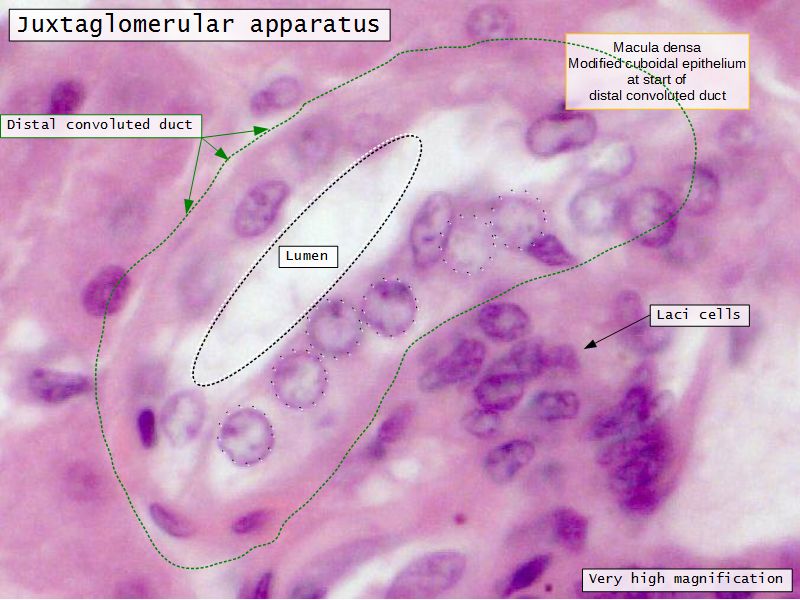

Juxtaglomerular complex

Area where distal convoluted tubule return to glomerulus and pass through the notch between the afferent and efferent arterioles. Modification of the wall of the tubule and afferent arteriole and presence of specialised cells in the connective tissue.Modifications

- Distal convoluted tubule

- Macula densa

- Narrow epithelial cells

- Nuclei densely packed

- CT cells

- Laci cells

- Similar to mesangial cells

- Afferent arteriole

- Modified smooth muscle cells

- Juxtaglomerular cells

- Secretory function